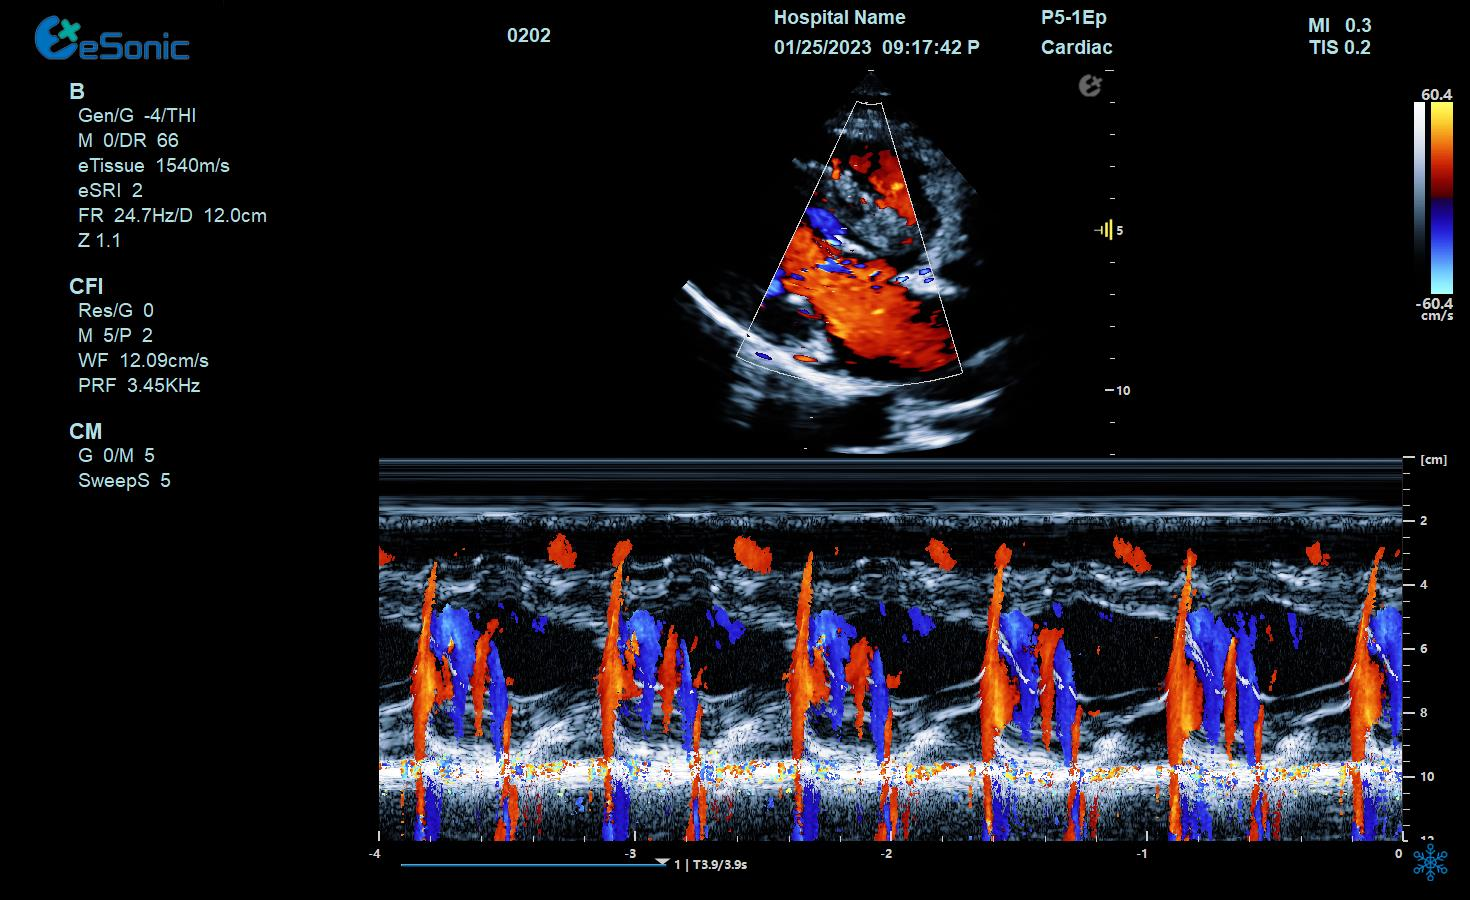

男性,82岁,临床诊断:风心病 房颤

超声表现:左房大,二尖瓣增厚、回声增强、运动僵硬;CDFI显示二尖瓣、三尖瓣、主动脉瓣返流信号。

风心瓣膜病二、三尖瓣关闭不全